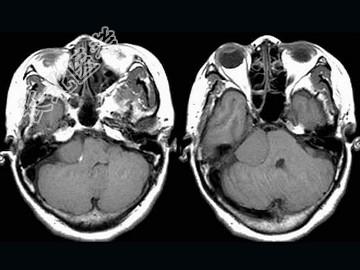

- 单项选择题女,57岁, 左侧听力进行性减退半年余,MRI检查如图, 最可能的诊断为 ( )

A、听神经瘤

B、三叉神经瘤

C、胆脂瘤

D、脑转移瘤

E、桥小脑角脑膜瘤